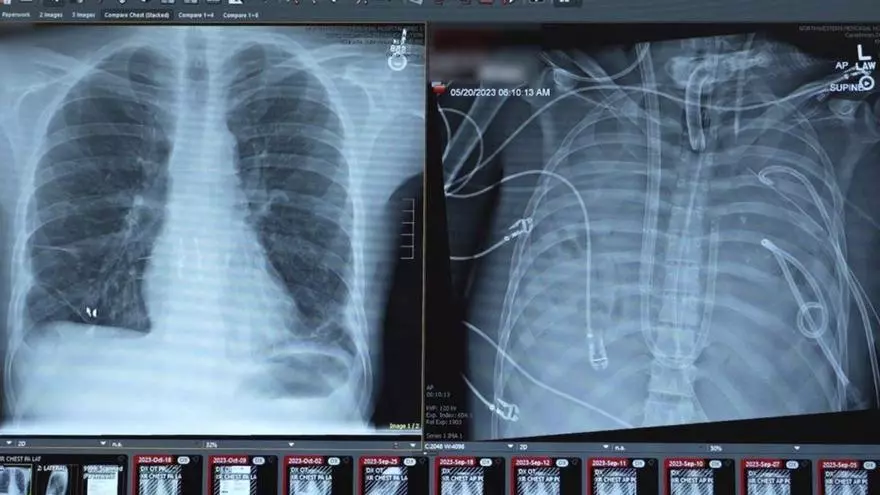

A la izq., imagen de los pulmones del paciente y a la derecha, el órgano artificial implantado. | Northwestern Medicine

En estos casos, afirman los especialistas, la tasa de mortalidad supera el 80 %. Y la única opción es realizar un trasplante bipulmonar. «El problema es que el paciente se encontraba demasiado inestable para recibir nuevos órganos», relatan los doctores que lo atendieron. «Además, sus pulmones estaban irreversiblemente dañados y actuaban como un foco activo de infección que agravaba la sepsis. Mantenerlos suponía un riesgo mortal pero, a su vez, retirarlos era prácticamente incompatible con la vida», relatan los especialistas. Fue entonces cuando los doctores decidieron tomar una estrategia arriesgada pero que, en este caso, se planteó como única herramienta para salvarle la vida. Un equipo liderado por el cirujano torácico Ankit Bharat, del Northwestern Medical Group, optó por desarrollar un sistema extracorpóreo de pulmones artificiales. Según explica el doctor, a diferencia de otras herramientas de soporte desarrolladas para otros casos, en esta ocasión se diseñó un dispositivo capaz de, por un lado, oxigenar la sangre y eliminar el dióxido de carbono y, por otro lado, reemplazar funciones clave de la circulación pulmonar. De esta forma, afirman los médicos, se consiguió que el corazón siguiera bombeando sangre de forma estable pese a la ausencia completa de pulmones.

Gracias a este sistema, los cirujanos pudieron realizar una neumonectomía bilateral, es decir, una operación para extirpar ambos pulmones y eliminar así la fuente de la infección. Los médicos afirman que tras la cirugía el estado del paciente mejoró de forma notable, se estabilizó su presión arterial, disminuyó la necesidad de fármacos para mantener el corazón y otros órganos comenzaron a recuperarse. «El sistema de pulmón artificial lo mantuvo con vida durante dos días completos», comentan los médicos.